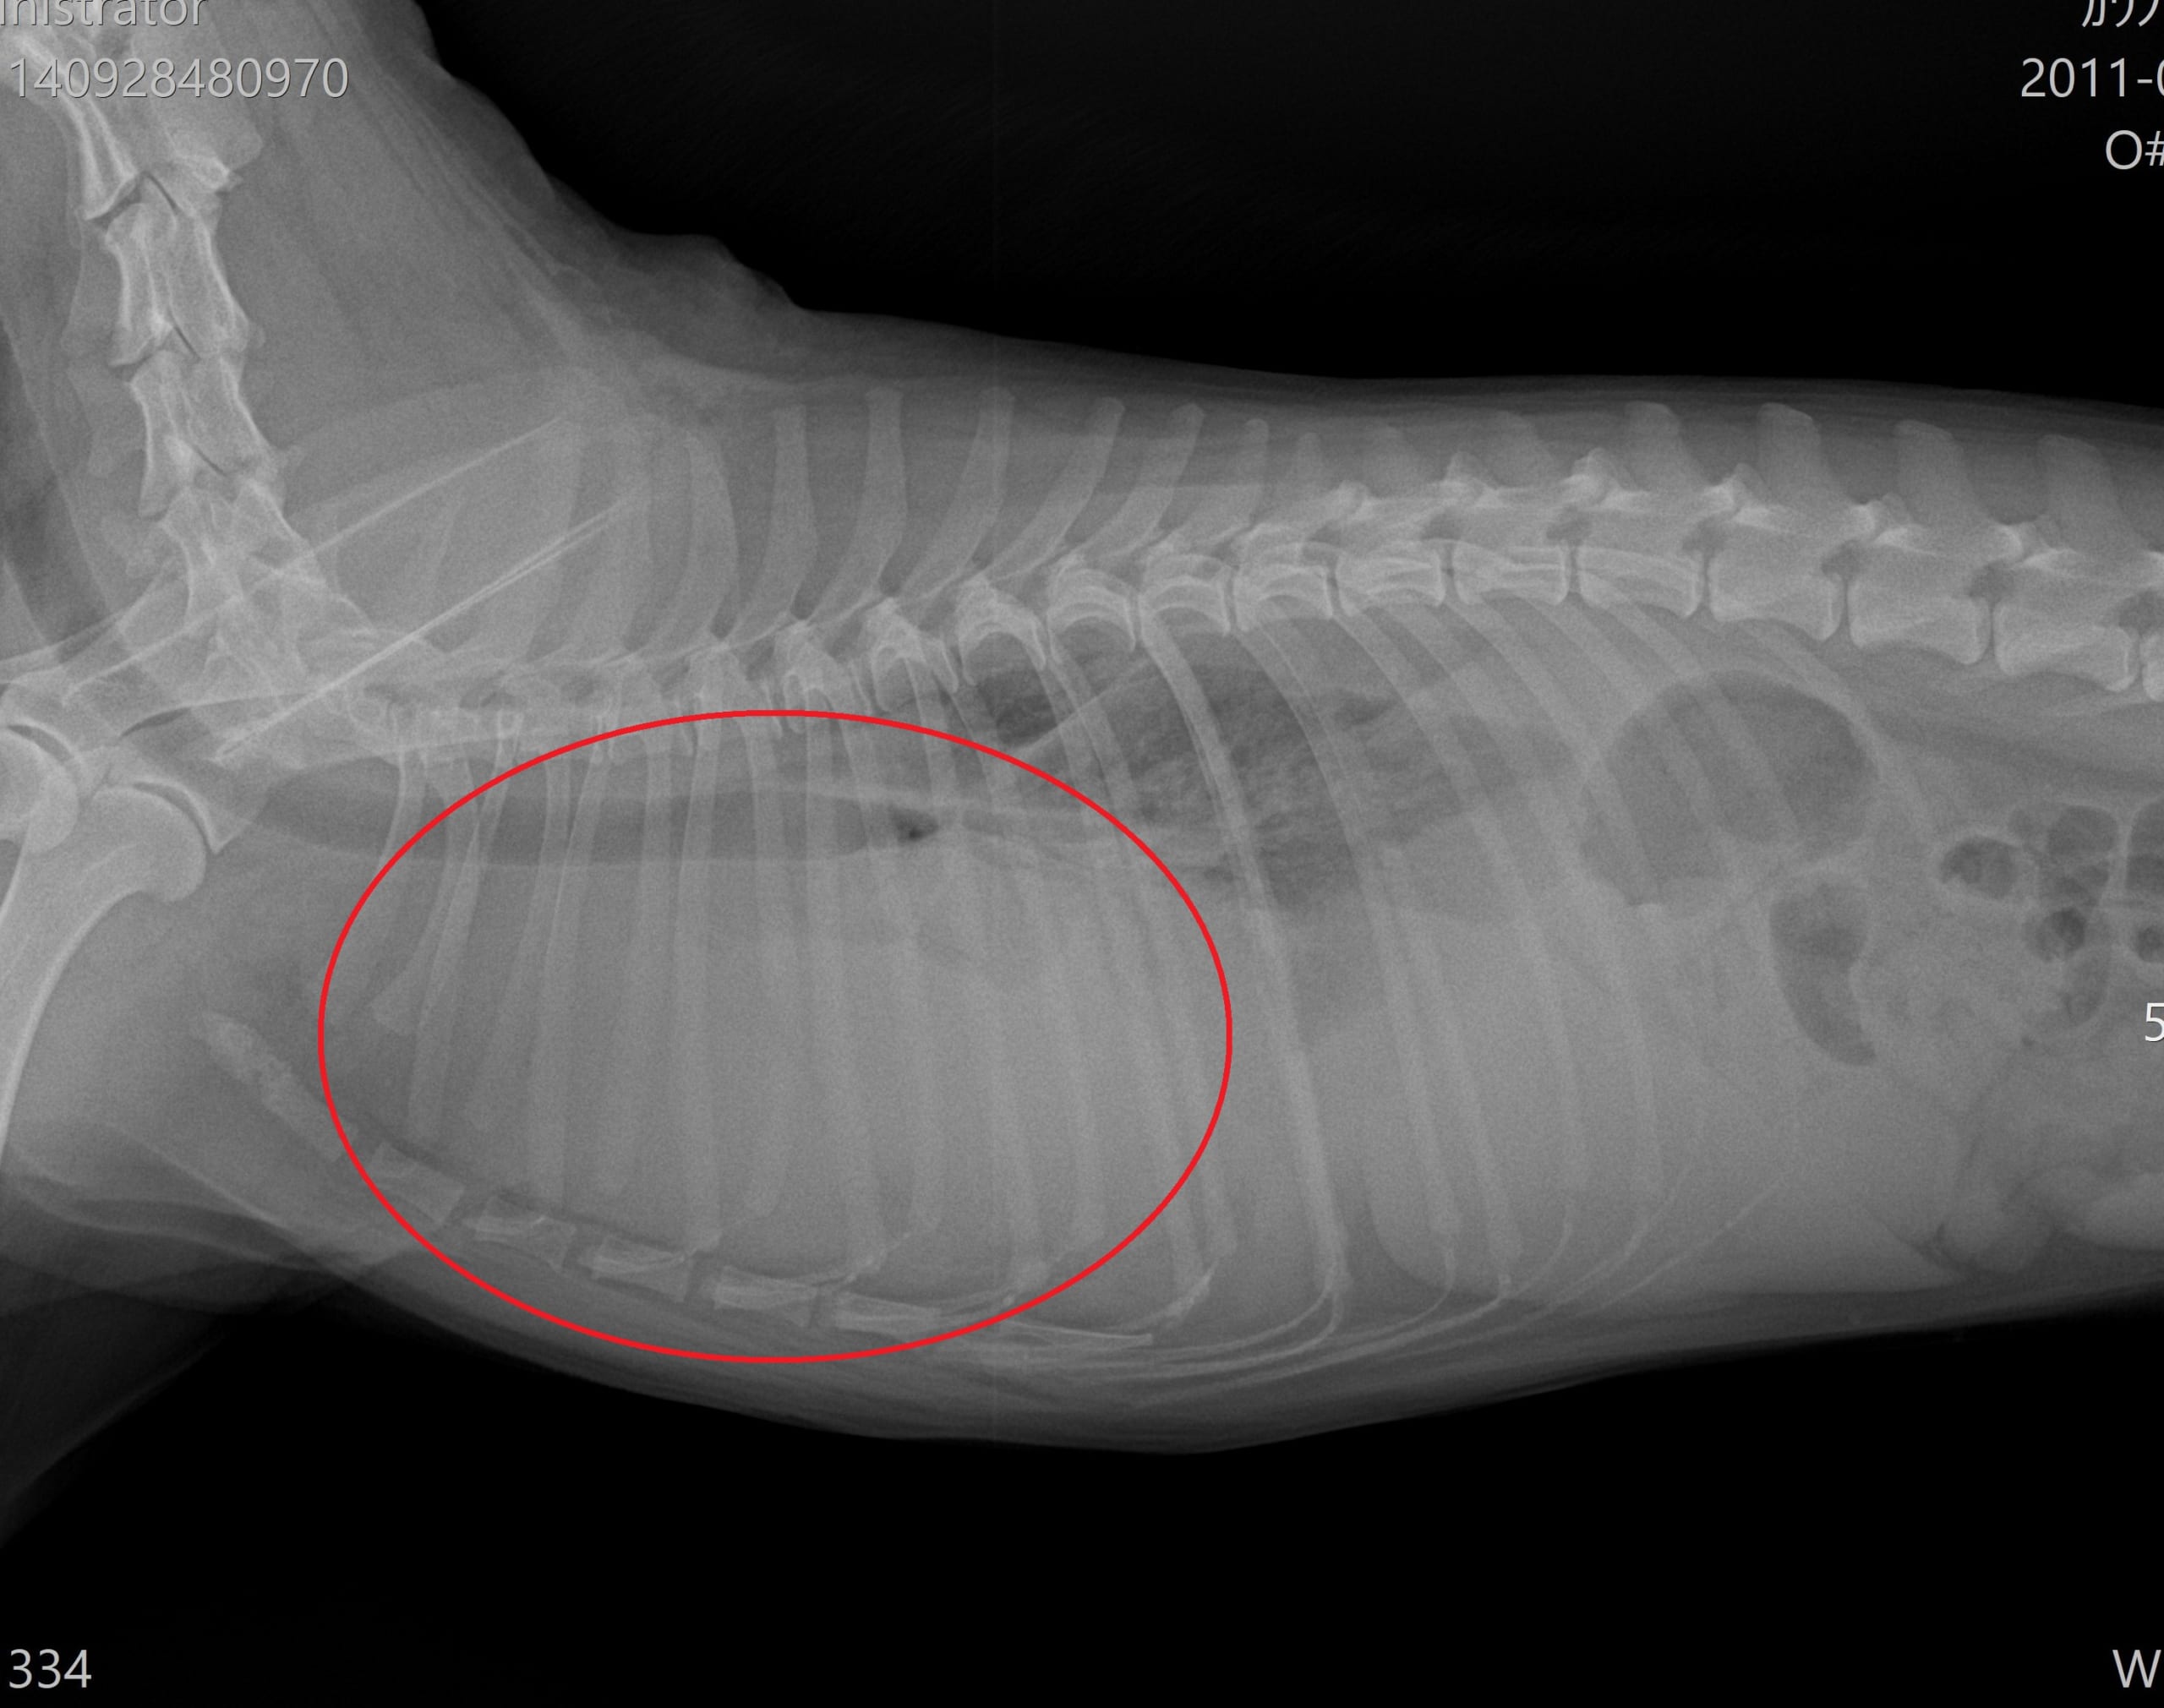

胸部レントゲン検査(腫瘤を赤丸で表示)

より詳しい評価が必要と判断し、沼津市の宮田動物病院にてCT検査をお願いしました。迅速に対応していただき、すぐにCT撮影を行っていただきました。

画像中の黒矢印で示した黄色の部分が、前胸部に認められた腫瘤です。